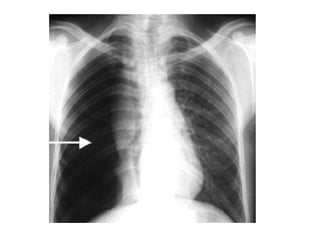

Neumocomiosis